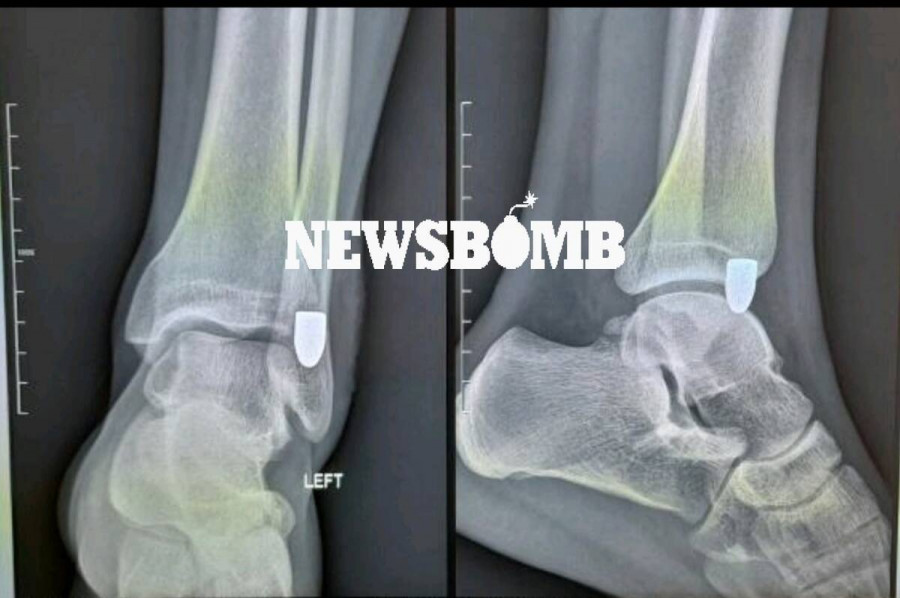

Φωτογραφία - ντοκουμέντο από την «αδέσποτη» σφαίρα που «καρφώθηκε» στο πόδι Δανού τουρίστα, ο οποίος βρισκόταν τα ξημερώματα της Κυριακής στο Γκάζι στο κέντρο της Αθήνας, δημοσιεύει το Newsbomb.gr.

Ο τραυματίας διακομίστηκε στο νοσοκομείο, όπου η ακτινογραφία έδειξε καθαρά την «καρφωμένη» σφαίρα στο πόδι του.